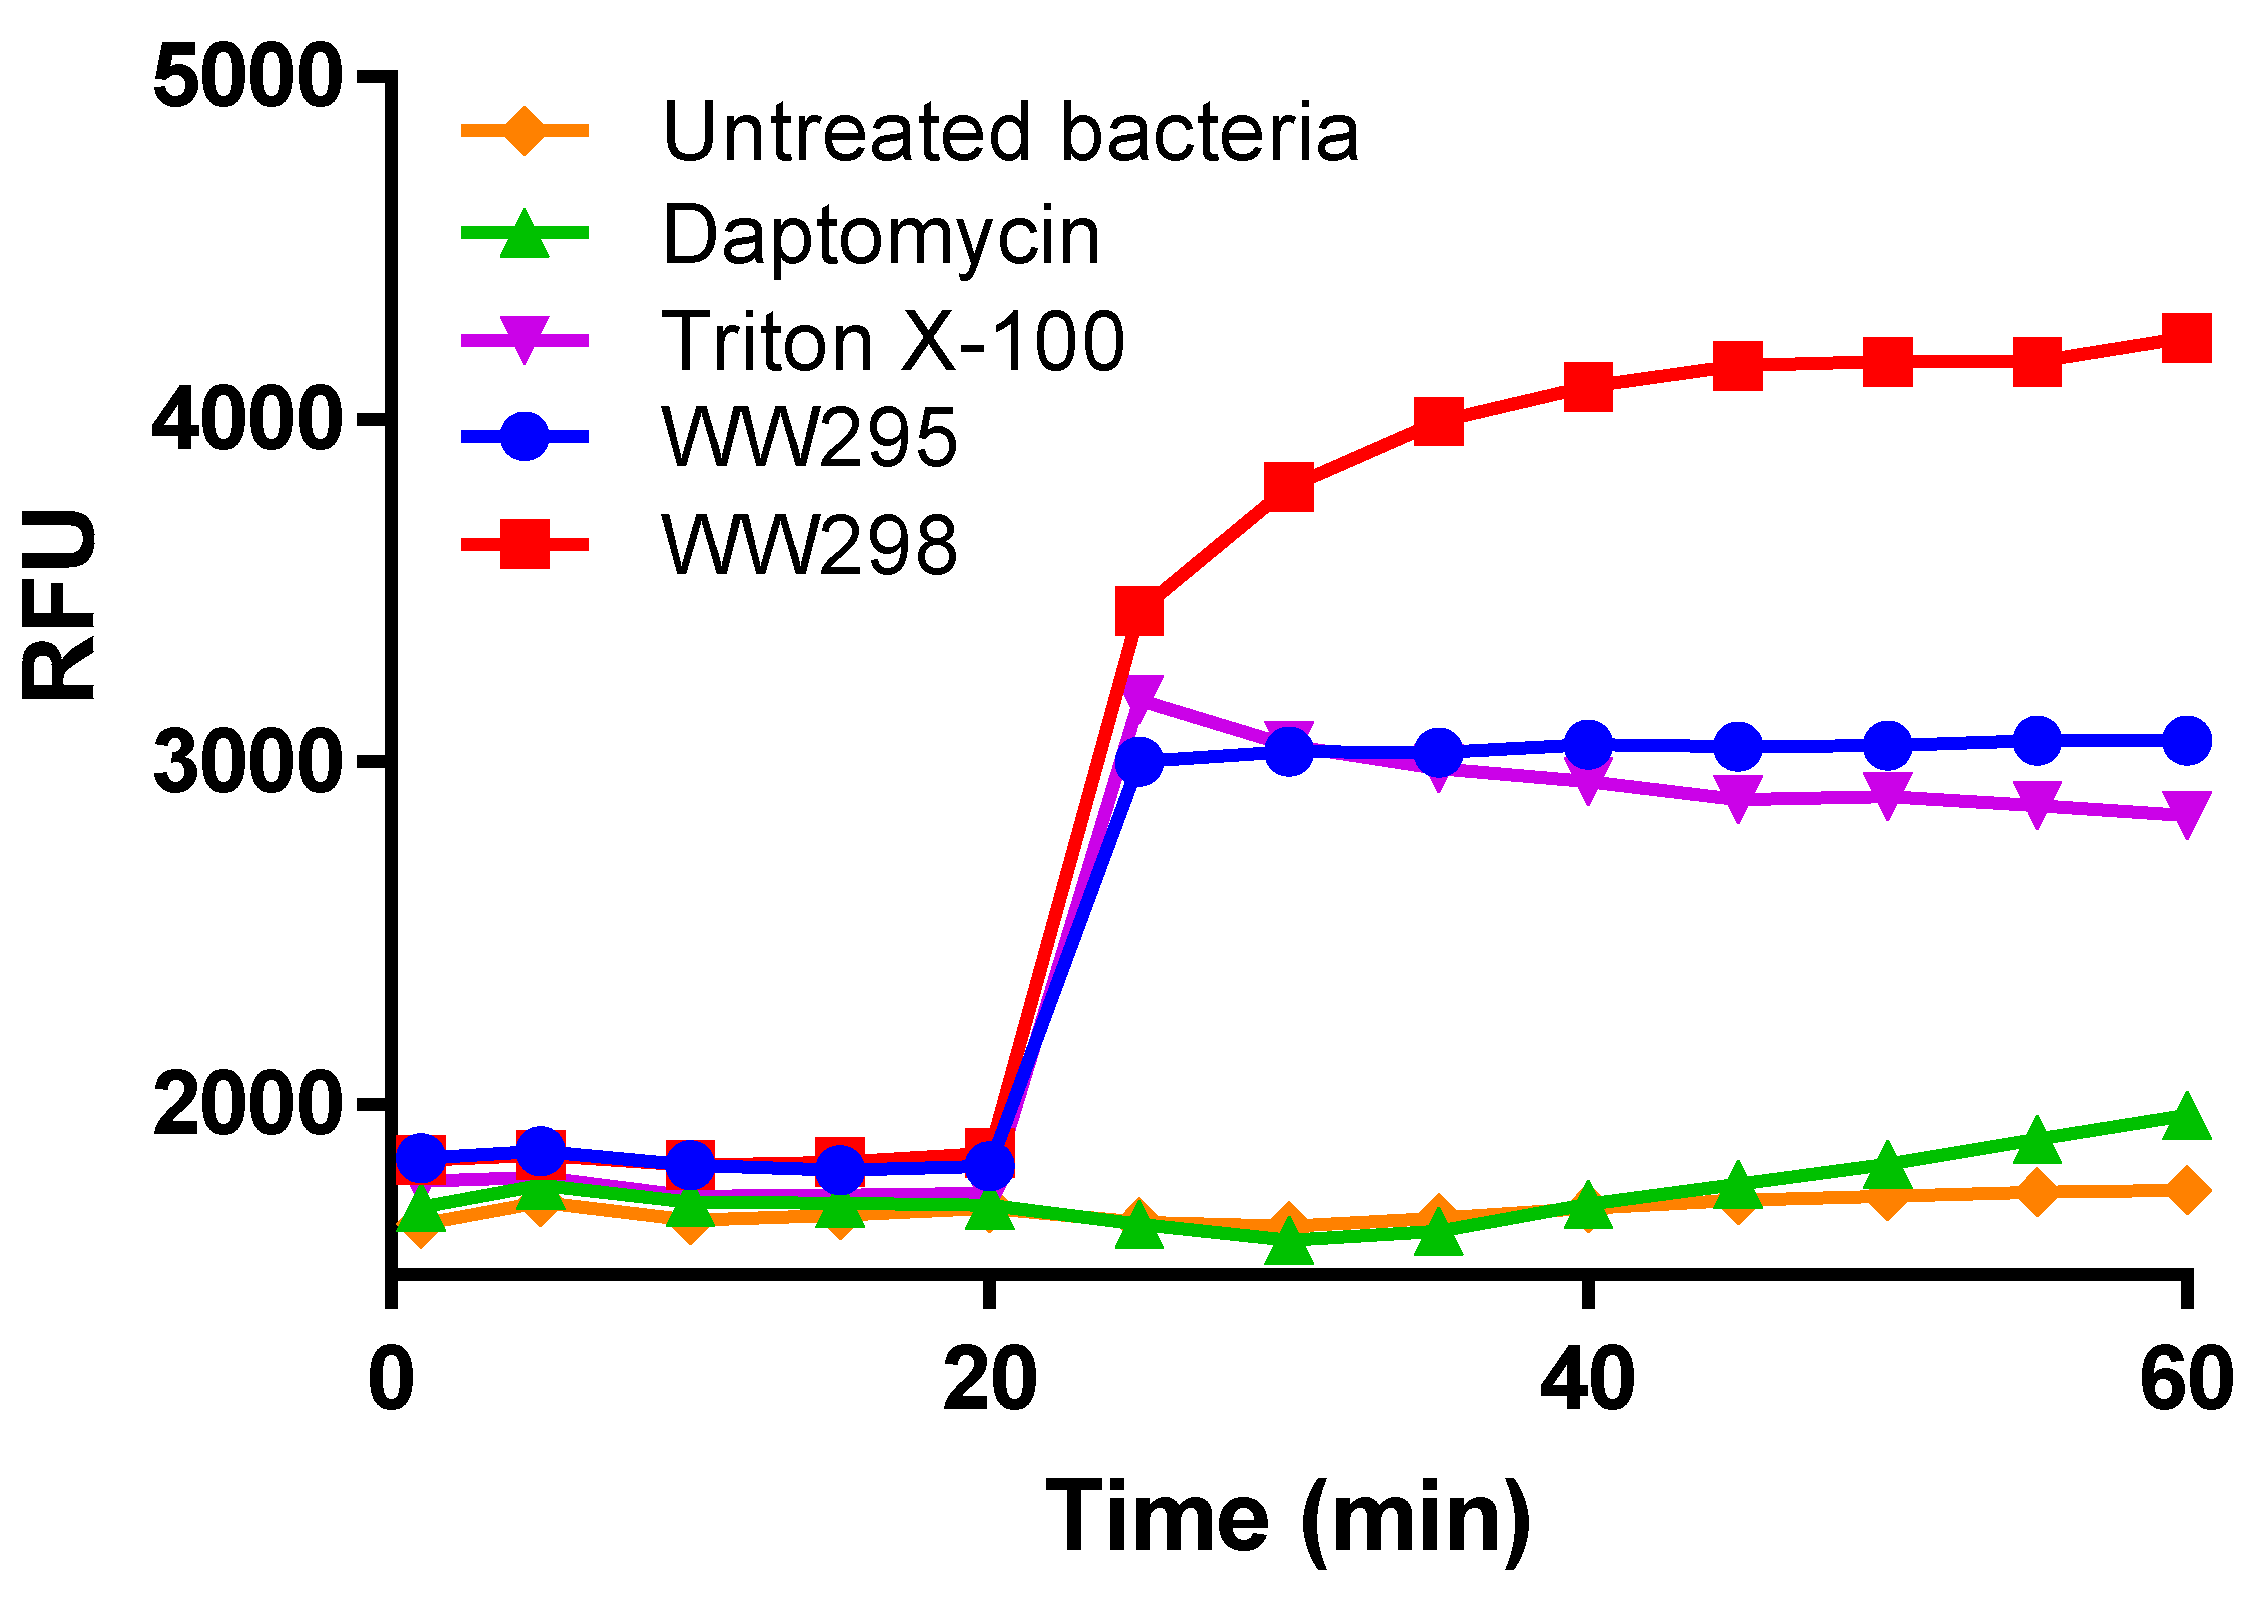

2.4. Propidium Iodide-Based Membrane Penetration Assay

2.6. Evidence of Membrane Depolarization of S. aureus USA300

4.9. Membrane Depolarization of Bacteria